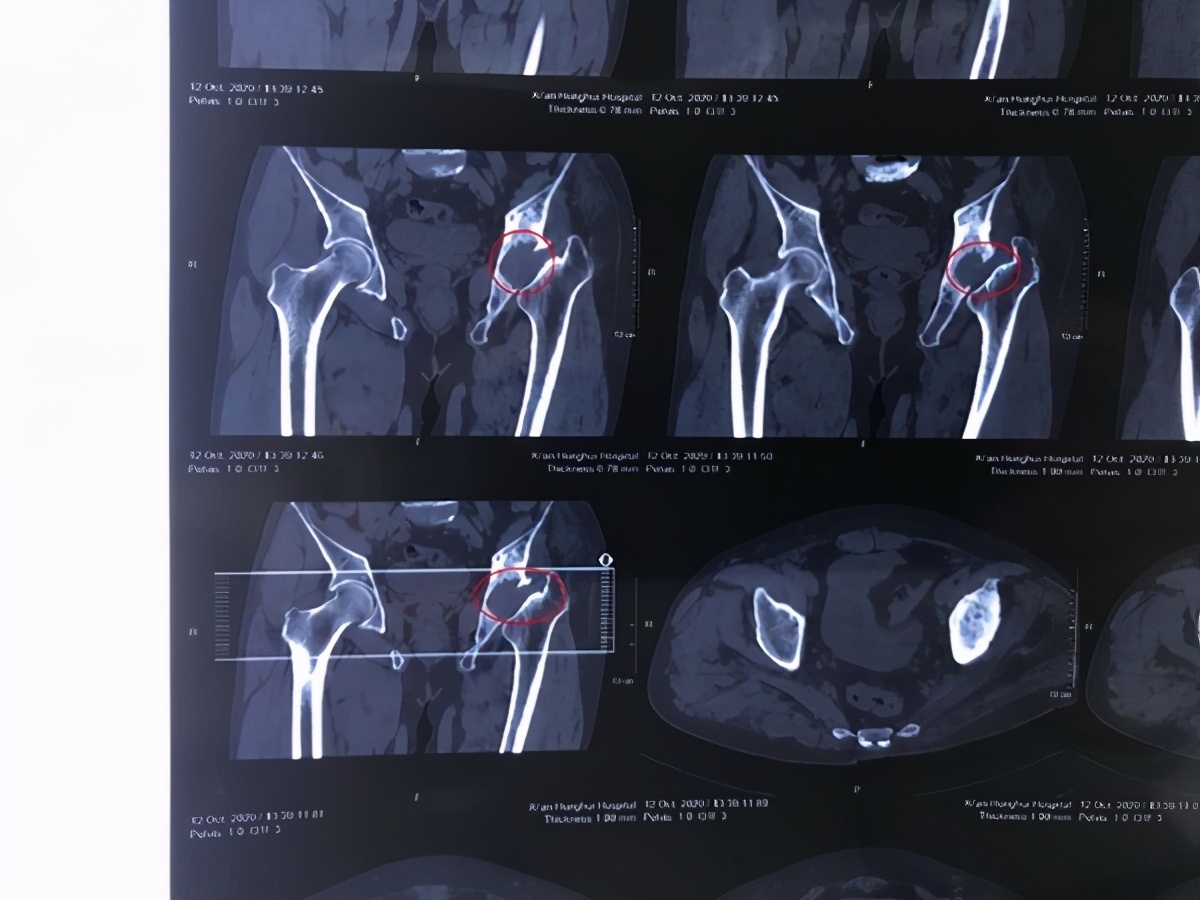

见到王先生,红会医院关节病医院骨坏死与关节重建病区主任郝阳泉以为只是普通的股骨头坏死病人,但检查结果却让他大吃一惊,患者左侧髋臼是空的,股骨头不见了。郝阳泉说,以往见到的病例是股骨头塌陷萎缩居多,在没有任何干预和诱因导致股骨头完全消失的实属罕见。

与患者沟通后,郝阳泉判断,王先生的股骨头是因为长期患病不加以干预,所导致的股骨头被自身吸收、消失。检查发现,王先生左腿长度已经比右腿长度整整短缩了2厘米多,这才导致王先生走起路来一摇一跛。

为了解决王先生的疼痛和跛行,让他和正常人一样自如行走,郝阳泉决定为他“找回”股骨头,重建髋关节的结构和功能,进行微创全髋关节置换手术。术前郝阳泉对王先生的疾病进行了仔细检查,进一步排除其他原因,明确诊断,并对左侧髋关节进行了CT扫描,应用3D重建打印技术,以制定更详细的手术方案。经过对比、推敲以及应急预案的制定后,医院为王先生实施了目前较先进的基于快速康复技术支持的直接前入路全髋关节置换手术。术后第二天,王先生就能下地进行功能锻炼。他感慨着说:“我一颠一跛着走了10年,以为一辈子就这样了,真没想到自己还能正常走路。”